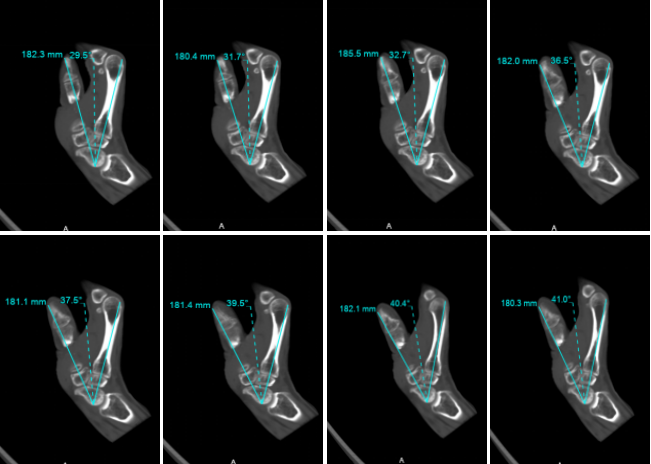

5、4D動(dòng)態(tài)成像

病例一 男,38歲, 拇指再植后運(yùn)動(dòng)障礙

患者拇指運(yùn)動(dòng)連續(xù)掃描采集的矢狀位重建圖像,能夠很好地顯示:再植后的拇指,主動(dòng)運(yùn)動(dòng)的掌側(cè)外展角度的變化范圍都明顯受限。

640層寬體探測(cè)器CT對(duì)于一些骨骼系統(tǒng)的疾病能夠單圈覆蓋。特殊的動(dòng)態(tài)掃描技術(shù),實(shí)現(xiàn)對(duì)于一些關(guān)節(jié)運(yùn)動(dòng)的量化分析。

在一些復(fù)雜的關(guān)節(jié)中,運(yùn)動(dòng)過(guò)于復(fù)雜,可能包含了多個(gè)運(yùn)動(dòng)結(jié)構(gòu)以及旋轉(zhuǎn)運(yùn)動(dòng), 甚至在關(guān)節(jié)振幅的極端處進(jìn)行靜態(tài)評(píng)估時(shí),不足以證明病變時(shí),動(dòng)態(tài)CT都能夠在制定運(yùn)動(dòng)過(guò)程中記錄骨骼關(guān)系的短暫變化, 這對(duì)評(píng)估復(fù)雜運(yùn)動(dòng)特別有用。